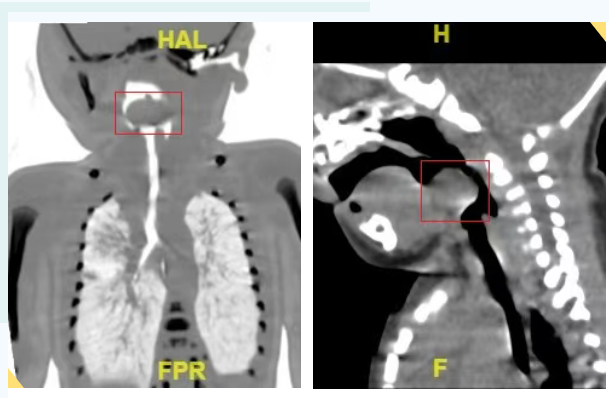

近日,临沂市妇幼保健院收治了一名会厌囊肿的新生儿。患儿出生两天因呼吸困难转入该院,CT显示在会厌上方有一个23×17×11mm的囊性区,这就好比是一颗悬在气管入口的“定时炸弹”,随时威胁患儿的生命安全。

经过医生的详细检查后发现,该患儿的会厌囊肿实在太大,占据了大半的口腔和咽腔,困难气道无疑,患儿几乎无法平躺,侧卧或者俯卧才能缓解缺氧。常规的麻醉用药方案有可能会造成无法通气无法插管的紧急状况,那么如何气管插管,是摆在麻醉医生面前第一要解决的难题。